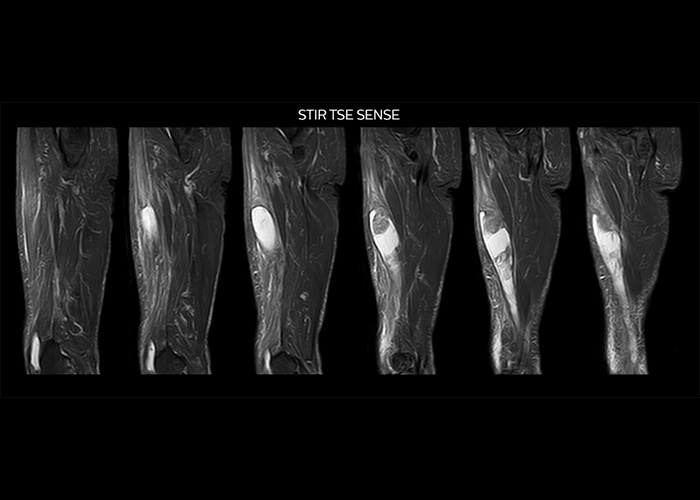

“On average, we scan about 80 patients per day, but on some days we scan well over 100 patients. The scanner is in use 7 days per week, operated 20 hours per day on week days and 8 hours per day in the weekend,” Mr. Tuna says. “To avoid coil changes we plan examinations of similar anatomies back to back, such as head and spine. Multiva helps us here a lot because coils don’t need to be changed frequently. Moreover, thanks to parallel imaging technology and 16-channel HeadSpineTorso and 8-channel MSK coils we are able to achieve excellent image quality. In this way Multiva helped us to increase both image quality and productivity.” “Neurological cases, such as brain and spine imaging, represent the largest share in our MR scanning, followed by musculoskeletal cases. In general, we use simple and basic imaging protocols. But occasionally, we use advanced techniques for problematic cases if necessary.